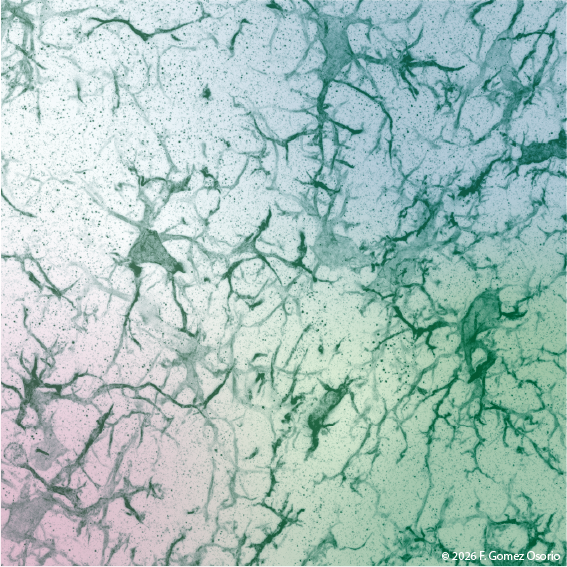

Mit unserer Forschung möchten wir helfen zu verstehen, wie sich Neuroinflammation und Hirnverletzungen auf die neuronale Funktion auswirken und die Reparatur- und Regenerationsfähigkeit des Gehirns beeinflussen, insbesondere im Zusammenhang mit dem Altern und Begleiterkrankungen. Die Projekte ermöglichen es die Frage zu klären: Warum passt sich sich das Gehirn in manchen Fällen erfolgreich an und erholt sich, aber in anderen Fällen scheitern Reparaturmechanismen? Wir untersuchen, wie entzündliche Prozesse im zentralen Nervensystem mit neuronalen Schaltkreisen interagieren und so die funktionellen Ergebnisse bei Erkrankungen wie Multipler Sklerose und Schlaganfall beeinflussen.

Daneben ist ein Schwerpunkt des Labors, zu verstehen, wie Alterung und Komorbiditäten die Anfälligkeit des Gehirns beeinflussen - indem sie zum Beispiel die Netzwerkdynamik und die oszillatorische Aktivität stören und die Regenerationsfähigkeit einschränken. Durch die Kombination von Modellen chronischer Neuroinflammation und akuter Hirnverletzungen wollen wir gemeinsame Mechanismen identifizieren, die neuronale Dysfunktion, Netzwerkanpassung und Reparatur steuern.

Wir untersuchen, wie Immun- und Gliazellreaktionen neuronale Schaltkreise bei entzündlichen Erkrankungen des Nervensystems wie Multipler Sklerose beeinflussen. Dabei interessieren uns